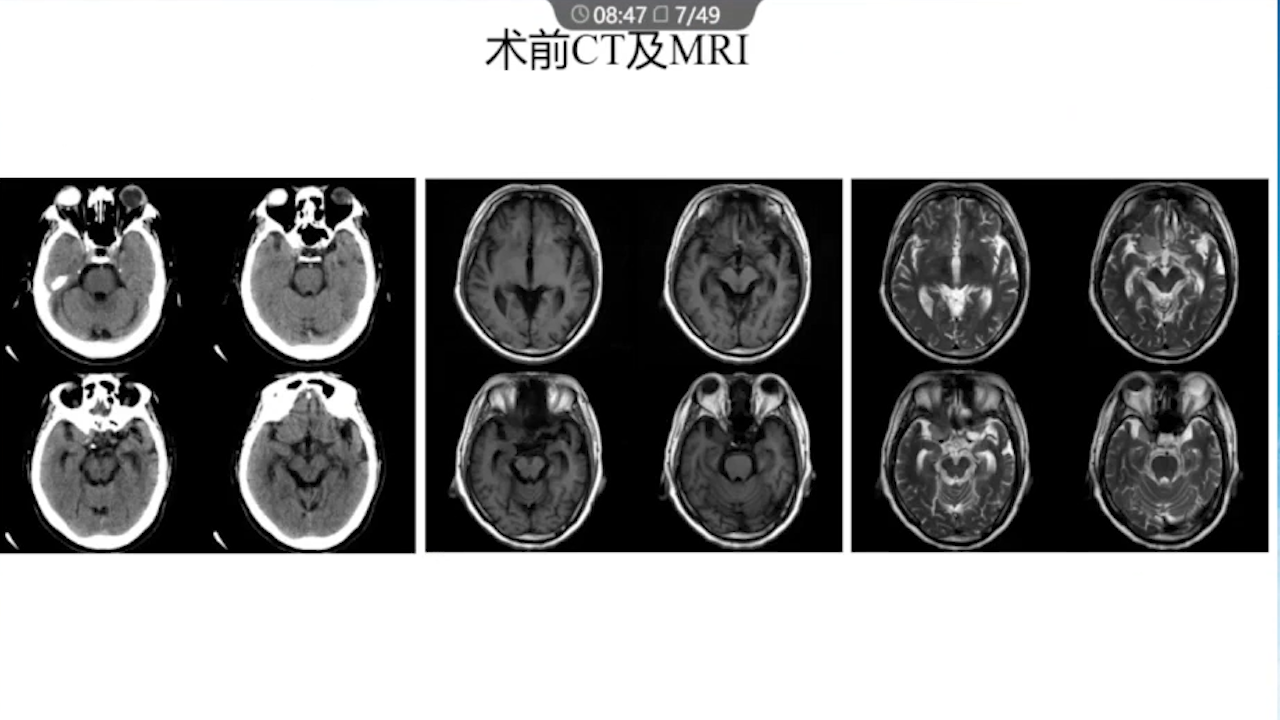

1、术前需要完善的影像学检查、多模态融合及神经导航以进行精确的肿瘤及静脉血管定位。